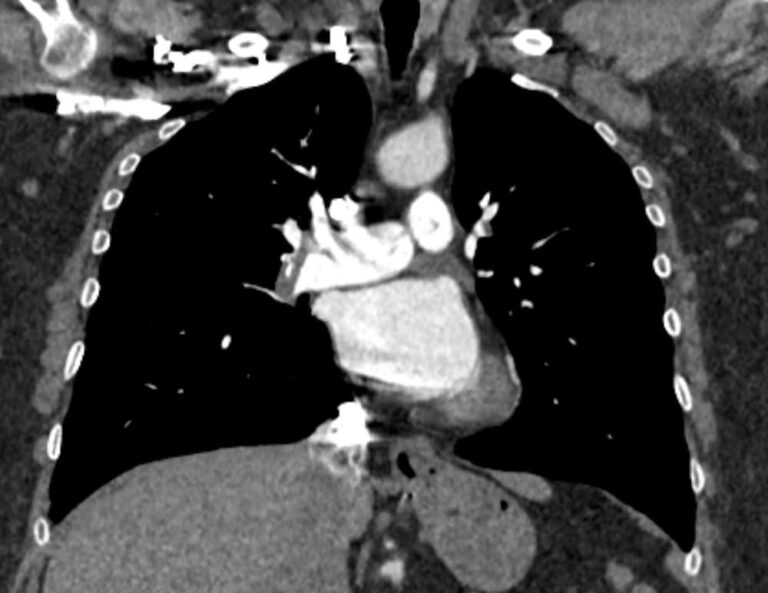

Тромбоэмболия легочной артерии характеризуется закупоркой просвета легочной артерии (либо самого легочного ствола, либо более мелких ветвей) тромбом. Тромб может образоваться в глубоких венах нижних конечностей, малого таза, часто после травм, операций, родов, а также в правом предсердии (на фоне нарушений сердечного ритма) и с током крови попадает в систему легочной артерии.

ТЭЛА может стать причиной внезапной смерти, а в некоторых случаях может приобретать хронический характер, когда тромбы малого размера закупоривают мелкие легочные артерии. В любом случае своевременная диагностика ТЭЛА может спасти жизнь больного.

Наиболее информативным, при этом быстрым и неинвазивным (то есть без вмешательства в организм пациента), методом диагностики патологии легочной артерии является мультиспиральная компьютерная томография (КТ-ангиография). Методика основана на использовании рентгеновского излучения в сочетании с цифровой обработкой данных для получения трехмерных изображений сосудистой системы.

Для визуализации кровеносных сосудов в обязательном порядке применяется контрастное усиление. Для этого в вену пациента вводится йодсодержащий контрастный препарат, который попадая в кровоток активно поглощает рентгеновские лучи и ярко контрастирует сосудистую систему, в том числе легочной артерии, на фоне окружающих тканей. Использование контраста дает возможность визуализировать даже мелкие артерии и выявить патологию.